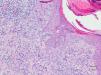

HistopatologíaSe realizó una biopsia punch de una de las lesiones que mostró un infiltrado inflamatorio en la dermis superficial formado por histiocitos, algunas células gigantes multinucleadas y linfocitos con expresión de marcadores inmunohistoquímicos tanto T como B, sin atipias destacables y sin observarse la presencia de linfocitos en la epidermis. Se pudo objetivar degeneración de las fibras de colágeno con un discreto depósito de mucina. En algunas áreas de la lesión se observaba una interrupción de la epidermis, a través de la cual se eliminaba un material compatible con colágeno degenerado (H-E, ×100) (fig. 2).